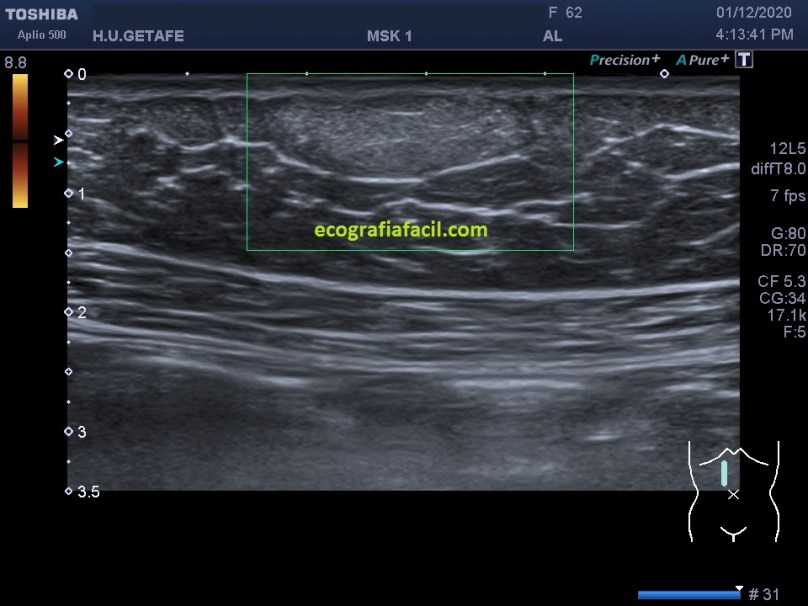

Normalmente encontraremos una lesión bien definida, hiperecogénica o isoecogénica con los márgenes definidos, en ocasiones lobulados, pero casi siempre ovalados con su eje largo paralelo a la piel en el plano subcutáneo y sin vascularización. Así, mira:

La estructura que estamos estudiando en este Caso 1, en las imágenes 1 a 6, es el estudio de protocolo de cualquier lesión, localización (flechas rosas), medición, vascularización. La 7 te marca una situación habitual en el estudio de los lipomas, y es que la paciente se nota un bulto, pero en la misma exploración descubrimos más, como es la pequeña lesión hiperecogénica que está justo al lado de la lesión mayor y palpable. Algunos de ellos, repito, pueden ser imperceptibles para la paciente, como era este caso. La imagen 8 es otra lesión próxima que sí era palpable.

En este caso las lesiones son todas hiperecogénicas comparativamente con el tejido hipoecogénico de la grasa del tejido celular subcutáneo. Son más o menos ovaladas, su eje largo es paralelo a la piel, no tienen vascularización y tienen medidas distintas. El diagnóstico final fue de lipomas. La paciente tenía más en la extremidades.